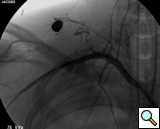

transected artery visualizing the pseudoaneurysm (Figure 2). A Viabahn covered stent (W.L. Gore & Associates, Flagstaff, AZ) is chosen for the appropriate size of the native vessel being careful not to oversize the stent graft. The stent graft is advanced across the lesion. Selective angiograms through the sheath may be performed to choose correct placement and appropriate landing zones. The stent graft is deployed under fluoroscopic visualization. Next, we utilize an appropriate sized 10 mm low pressure balloon to “iron out the edges” of the stent and bring it up to profile of the artery (Figure 3). Next, completion angiograms are performed to rule out endoleak and complete exclusion of the pseudoaneurysm, as well as to confirm distal runoff to the forearm and palmar branches of the extremity (Figure 4).

![]() |

| Figure 4: Post-deployment of the stent with 10 mm balloon brought up to vessel profile. |